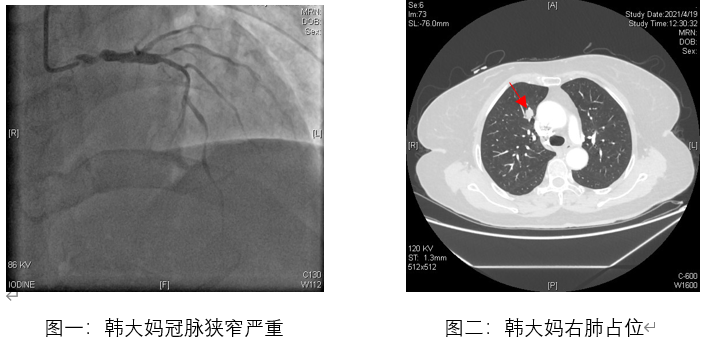

北京清华长庚医院5月17日电(通讯员 杨栩鹏)60多岁的韩大妈最近遇上了麻烦事儿。近几个月来,她在活动后出现了胸闷,嗓子仿佛被人勒住了,休息之后症状有减轻。刚开始她并没有把这事儿放在心上,后来随着症状出现得越来越频繁,一向自诩身体不错的她也决定去医院看看。当地医院做了心电图之后考虑有心肌缺血,冠脉造影也证实了韩大妈心脏上动脉狭窄严重,所以她近期的症状很有可能和心肌供血不足有关。由于她三根主要冠脉均有狭窄,支架已经不是首选治疗方案,而冠脉搭桥的获益更大。除此以外,这次住院意外地发现韩大妈的右肺上有一个占位,根据影像学判断恶性可能性比较大,也需要手术治疗。同期手术还是分期手术?如何在保证安全的同时,拥有最好的治疗效果?当地医院犯了难,于是建议韩大妈来北京治疗。

在韩大妈住院期间,心脏外科与胸外科进行联合会诊,仔细研究患者影像学资料,共同商议治疗方案。如果先做心脏手术会因为延误时间而造成肿瘤增大甚至转移,但先做肿瘤切除却因为心脏功能差而无法保证手术顺利,如果两种手术一起进行,难度绝不是简单的1+1="2,不但要求专科医生具有精湛的手术技术,而且还需要两科室的默契配合。鉴于冠脉搭桥需正中开胸,胸外科陈东红主任决定同期以此切口作为手术入路,切除病变的肺段,清扫相关区域淋巴结。联合手术虽然延长了本次手术时间,但避免了韩大妈二次手术风险,远期受益明显。